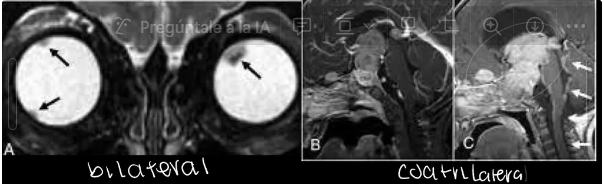

¿de qué enfermedad nos habla la siguiente imagen?

retinoblastoma bilateral y cuadrilateral

Cuantos subtipos de retinoblastoma existen

Trilateral: retinoblastoma bilateral + tumor neuroplástico (en glandula pineal)

Cuadrilateral: retinoblastoma bilateral + tumores pineales y supraselares (en región supraselar)